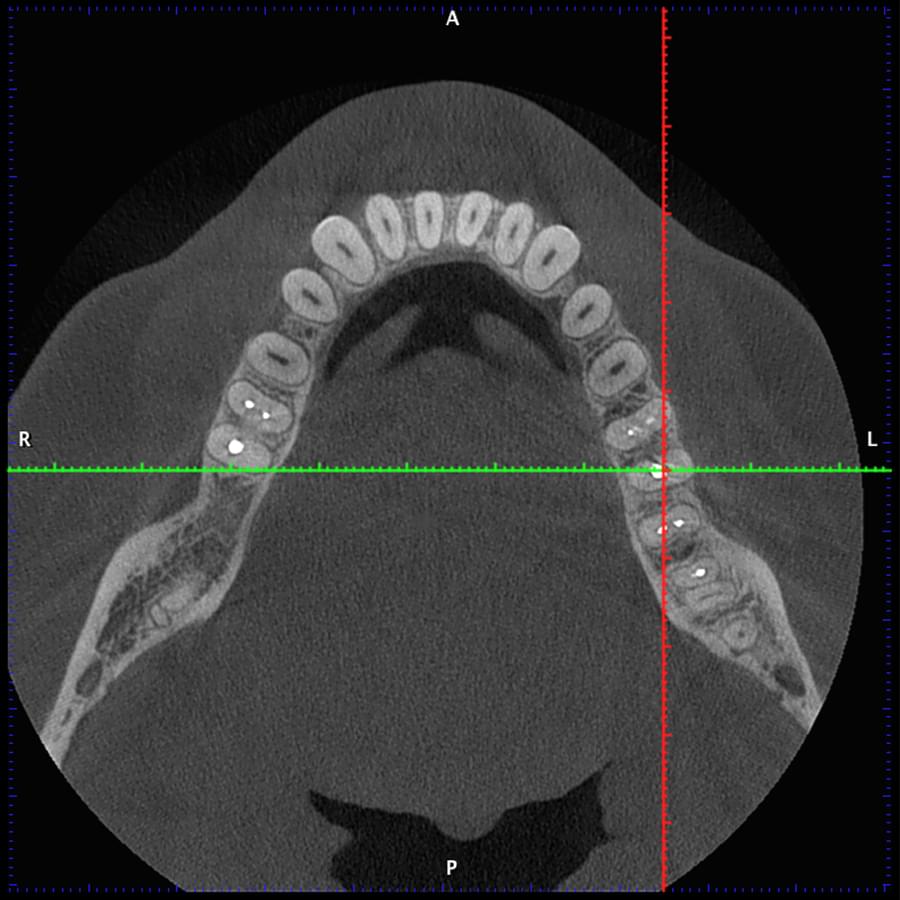

Отримайте вичерпну інформацію про стан ЛОР-органів завдяки надточній діагностиці на апараті

PLANMECA. Наші знімки дозволяють детально візуалізувати всі групи навколоносових синусів,

структури остіомеатального комплексу та анатомію носової перегородки.

Ми надаємо не просто знімок, а повний діагностичний сервіс:

Детальний опис: Кожне дослідження супроводжується професійним висновком лікаря-рентгенолога

з описом виявлених патологій (кісти, поліпи, сторонні тіла, рівень рідини, потовщення

слизової).

Зручна візуалізація: Можливість перегляду структур у будь-якій проекції (аксіальній,

корональній, сагітальній) для точної локалізації запального процесу.

Весь архів досліджень ваших пацієнтів надійно зберігається на вашому персональному хмарному

диску на нашому сервері — доступно в один клік у будь-який момент.